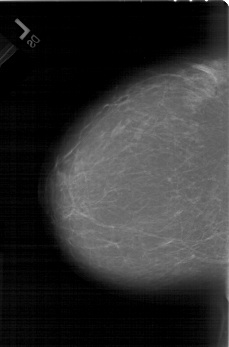

A_1440_1.RIGHT_MLO

LEFT_MLO LINES 6481 PIXELS_PER_LINE 4471 BITS_PER_PIXEL 12 RESOLUTION 43.5 NON_OVERLAY